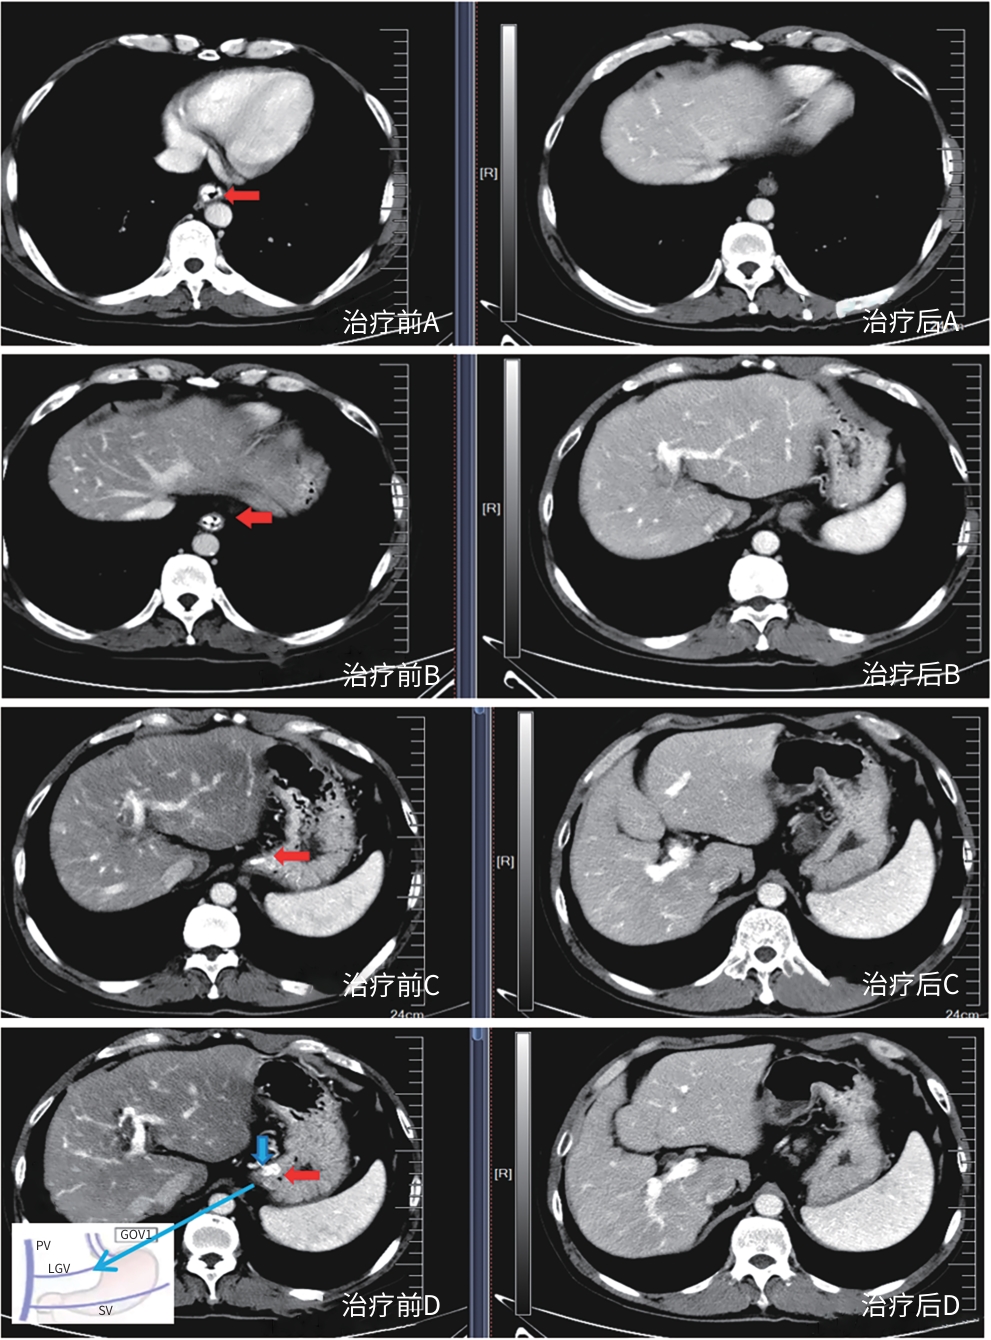

•   Objective  To investigate the safety and efficacy of puncture cyanoacrylate selective seal (PCSS) under endoscopic ultrasound in the treatment of gastroesophageal varices (GOV).  Methods  A total of 100 patients with liver cirrhosis who underwent endoscopic therapy for the secondary prevention of GOV bleeding in Beijing Ditan Hospital, Capital Medical University, from March 1 to December 31, 2023 were enrolled and randomly divided into PCSS group and traditional endoscopy group. The patients were followed up for 6 months after surgery, and the two groups were compared in terms of clinical outcome and complications. The primary outcome measure was the rate of alleviation or disappearance of GOV, and the secondary outcome measure was variceal rebleeding and death. The independent-samples t test was used for comparison of normally distributed or approximately normally distributed quantitative data between two groups, and the Wilcoxon non-parametric test was used for comparison of non-normally distributed quantitative data between two groups; the chi-square test or the Fisher’s exact test was used for comparison of qualitative data between two groups.  Results  There were 50 patients in the PCSS group, among whom 1 patient was lost to follow-up, and there were 50 patients in the traditional endoscopy group, among whom 3 patients were lost to follow-up. There were no significant differences between the two groups in baseline data such as age, sex, Child-Pugh class, varices grade, and GOV typing (all P>0.05). Compared with the traditional endoscopy group, the PCSS group had significantly better results of the number of endoscopic treatment sessions (t=-15.671, P=0.001), the total amount of tissue adhesive used (t=-2.830, P=0.006), and the rate of alleviation or eradication of varices sclerosis (χ2=7.078, P=0.029). Both groups had low rates of postoperative rebleeding, adverse reactions, and complications, and there were no significant differences between the two groups (all P>0.05).  Conclusion  Compared with traditional endoscopy, PCSS can significantly enhance treatment outcome while maintaining safety standards.